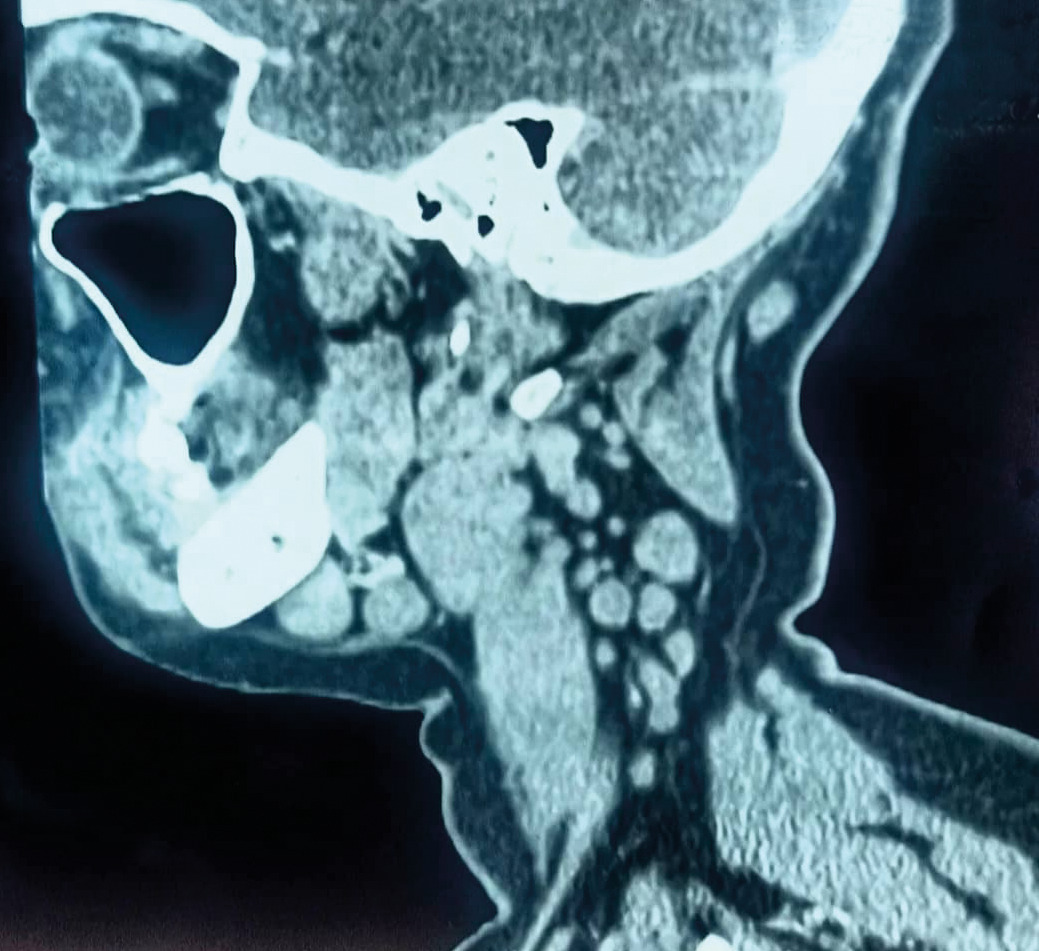

Une patiente âgée de 40 ans est admise à l’hôpital pour exploration d’adénopathies cervicales. L’interrogatoire révèle une obstruction nasale chronique accompagnée d’une rhinorrhée. L’endoscopie met en évidence une rhinite croûteuse avec un bombement du cavum (fig. 1). La tomodensitométrie montre un cavum pseudotumoral (fig. 2, 3 et 4). L’histologie objective un processus granulomateux tuberculoïde (fig. 5). Le GeneXpert sur fragment de biopsie, l’intradermoréaction à la tuberculine et la recherche de bacille de Koch dans les crachats sont négatifs.

La calcémie, la protéine C-réactive (CRP), l’angiotensine convertase et le bilan immunologique sont normaux. La confrontation des données cliniques, radiologiques, histologiques et biologiques retient le diagnostic de sarcoïdose. L’évolution a été favorable sous corticothérapie systémique.

La sarcoïdose est une granulomatose multisystémique, d’étiologie méconnue. La sphère ORL, en particulier le cavum, est une localisation très rare.1,2 Chez cette patiente, le diagnostic est retenu après élimination d’une néoplasie, de la tuberculose – endémique au Maroc – et des autres granulomatoses.